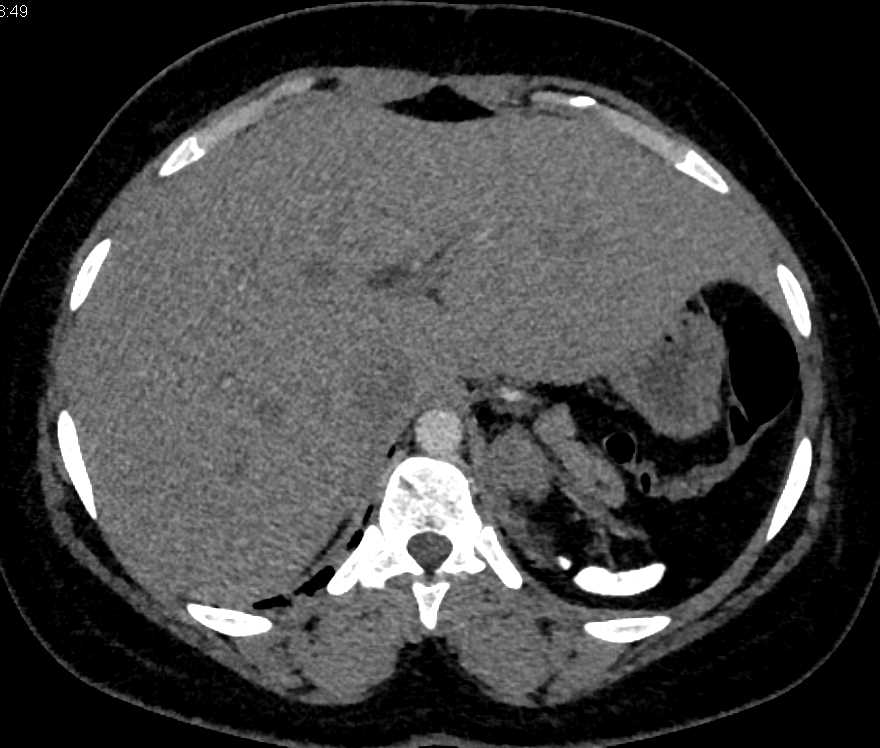

Gaucher's Spleen